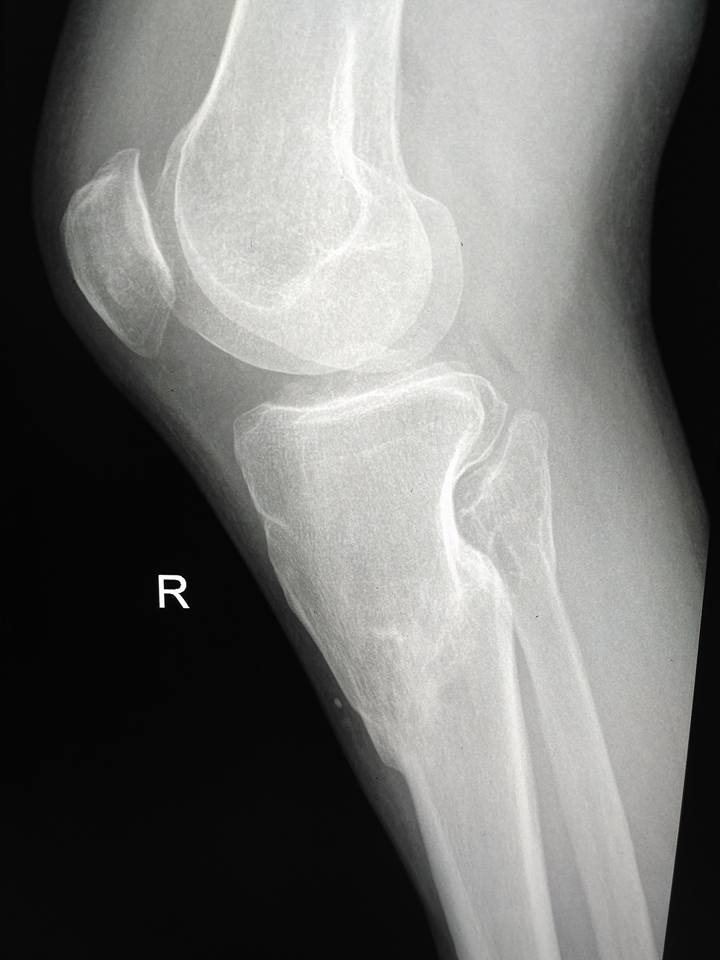

[Ortho] Псевдартроз tibia с варусной деформацией

Пациент мужчина 40 лет. Около 2-х лет назад травма. Лечили со слов

пациента гипсом, не было страховки, прописки и все было отягощено

хр.алкоголизмом.

Сейчас пациент встал так сказать на путь истинный, не пьет больше года,

выправил документы и хочет прямую ногу.

В области перелома в нижней трети подвижности практически нет, нога опорная.

Коллеги, какие мнения? Вопрос, стоит ли попытаться одномоментно

исправить ситуацию стержнем или растянуть сразу не удастся? Стоит ли

делать коррекцию в верхней трети?